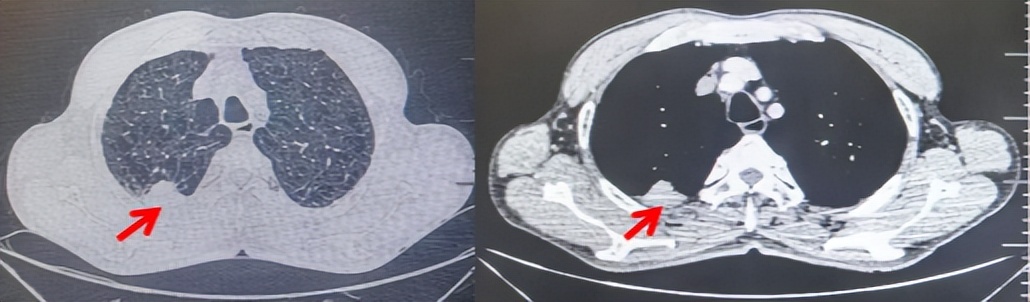

71岁男性,高血压病史20年,口服药物治疗,无糖尿病、心脏病等基础疾病,吸烟史50年,20支/天,已戒1年余,无饮酒史,无肿瘤家族史。2023.11因咳嗽、咳痰行胸CT检查:左肺下叶占位性病变,大小约12mmx8mm(如图5)。2023.11.20行“单孔胸腔镜左肺中下叶切除、肺门及纵隔淋巴结清扫、胸膜粘连松解术”;术后病理:(左肺下叶)结合免疫组化鳞状细胞癌(中、低分化),局部见脉管内癌栓,未见确切神经侵犯,(气管切缘)净。(淋巴结)未见转移癌0/19(4组0/1;5组0/1;6组0/2;7组0/1;9组0/1;10组0/2;11组0/3;12组0/2;13组0/2;14组0/4)。术后分期pT1bN0M0 IA期,术后定期复查。

图5:患者手术前(2023.11)胸部CT肺窗及纵隔窗